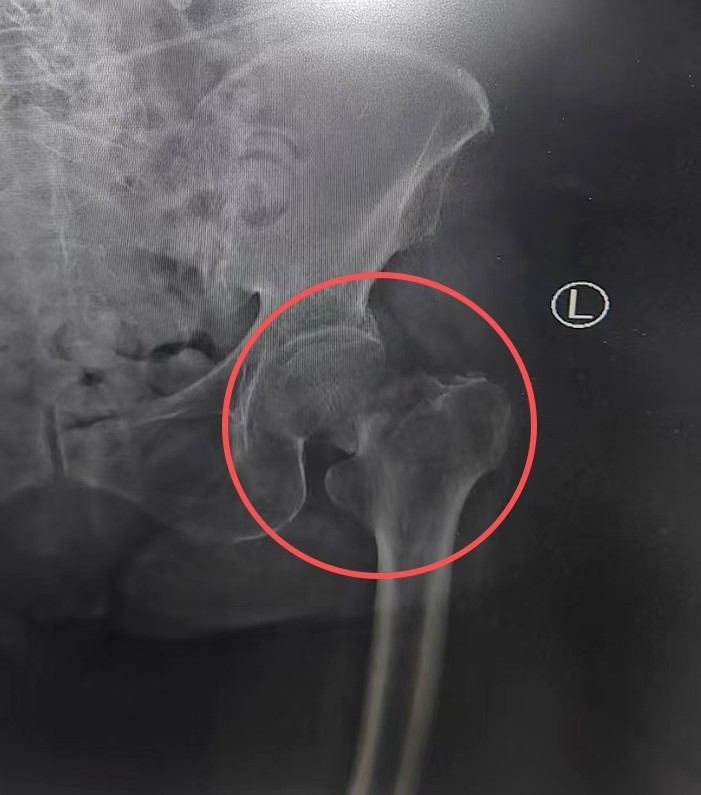

7小时前,刘奶奶在家中不慎摔倒,左髋部剧痛,动弹不得。家人火速将老人送至当地医院,X线检查显示:左侧股骨颈骨折。这个诊断对年轻人尚属严重,对97岁高龄的老人更是危及生命的重创。

“超高龄不是手术的绝对禁忌症。”刘大诚坚定地说。在麻醉科副主任、主任医师戴必照,副主任医师卢思宇等专家进行术前评估后,经过仔细讨论,团队最终决定迎难而上,在气管插管全麻下为老人实施左侧人工股骨头置换术。